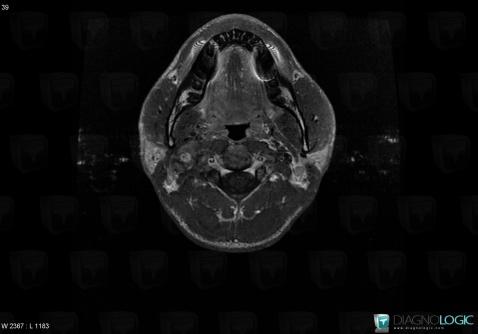

Schwannome, Espaces profonds-cou, IRM

Voici les informations spécifiques à l'image clé ci dessus:

- Diagnostic Schwannome, Localisation(s) Espaces profonds du cou, comportant les gammes Lésion de l'espace carotidien, Masse solide cervicale